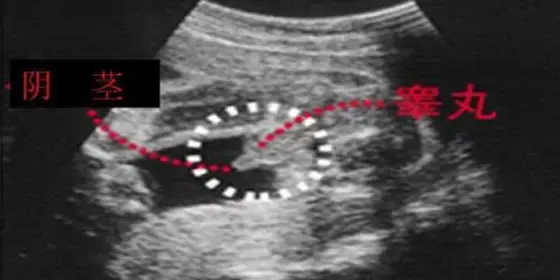

有人說啊,根據孕囊的形狀什么的可以看男女?

美滋滋拿到B超單,身邊的朋友或者老人會神乎其神地對著那方寸之地看了又看,根據孕囊的形狀什么的告訴你這寶寶的性別。

甚至網上啊,還煞有其事出現了教你根據孕囊判斷寶寶性別的方法:

▽

還會告訴你,這下面的三條白線是明顯的女寶特征,如果沒有看到明顯的三條白線,就看兩腿之間有沒有突出的東東,且中間有小凹槽的,就是女寶寶。???(真的假的?)

搜索了下,發現啊這五花八門的道道還真不少。

而這些,都可以肯定地告訴大家——沒有科學依據!

準媽媽們的孕囊看上去形狀有所區別與胎兒性別沒有關系。一般發育較好的孕囊是圓扁形的,但是有時孕囊會隨宮腔的形狀而變長。孕囊的形狀由其張力和含羊水量決定的,會自行改變形狀。

這樣,懷孕天數不同,看到的孕囊也可能不一樣。另外,每次B 超探頭的方向不同,從不同的角度看,孕囊的形狀也是不一樣的。

所以,將孕囊形狀和寶寶性別聯系在一起沒有根據,事實證明也不符。